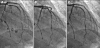

To illustrate the effect of myocardial bridges on coronary vascular tone, we describe the cases of 2 patients with different clinical presentations in the context of reproducible increased spasticity at the site of myocardial bridging. One had an episode of takotsubo cardiomyopathy, and one developed typical Prinzmetal angina while receiving desmopressin treatment for pituitary insufficiency. In both patients, acetylcholine challenge clearly revealed both the presence and the severity of myocardial bridging while producing several recognizable degrees of abnormal spastic tendency.Both baseline functional states and responses to different medications correlate with spastic tendency and enable the characterization of individual cases. Understanding the spectrum of spastic conditions might help to clarify the causes of atypical ischemic events, especially in patients with myocardial bridging.